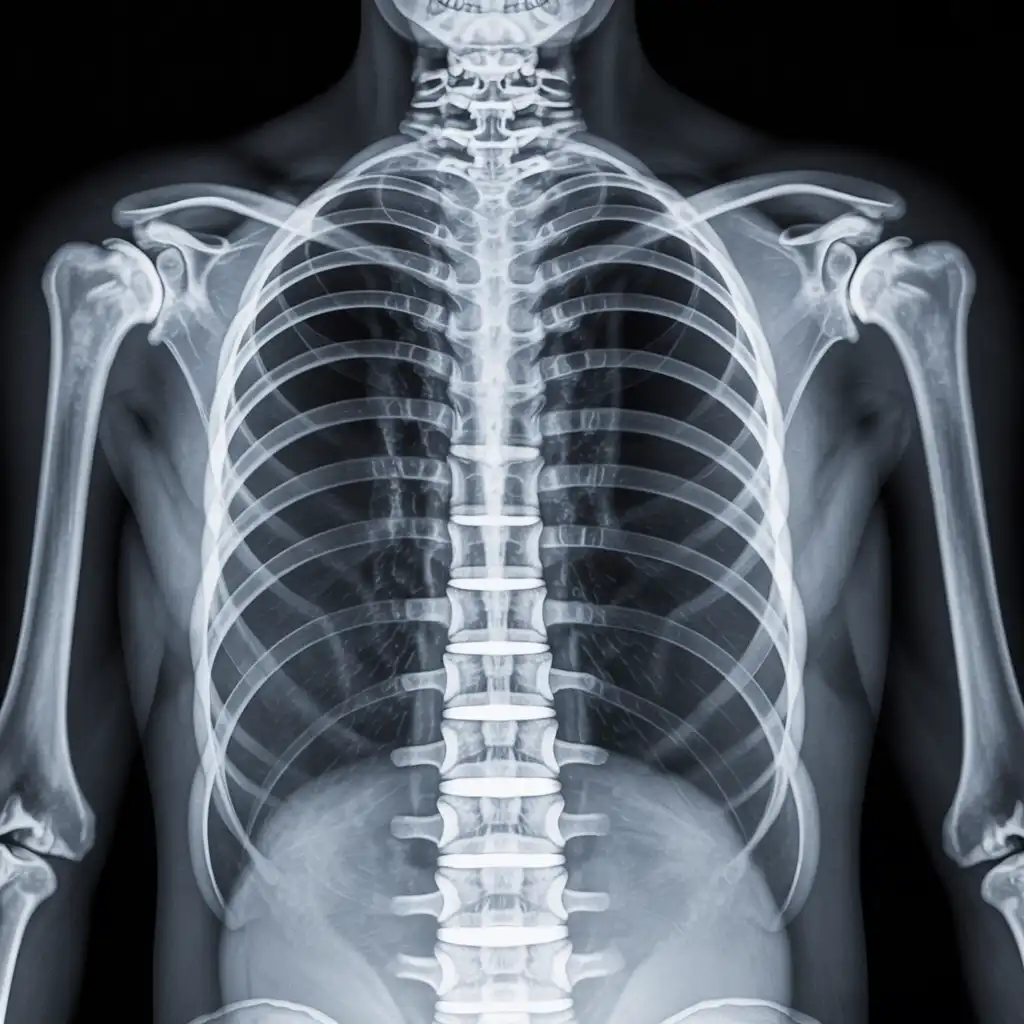

Il professionista entra con apparecchiature a basso dosaggio e schermi protettivi: bastano 2 × 2 m di spazio vicino al letto o alla poltrona. In pochi minuti acquisisce immagini HD, proprio come in un reparto ospedaliero.

Le immagini (formato DICOM) vengono caricate su un server crittografato e inviate immediatamente al radiologo. Se servono scatti aggiuntivi, il tecnico resta in collegamento video per eseguirli al volo.

Il medico radiologo analizza le immagini e firma il referto digitale all’istante. Ricevi il referto cartaceo e le immagini su chiavetta USB consegnati direttamente a casa tua subito dopo l'esame.

Usiamo le stesse apparecchiature certificate CE dei reparti ospedalieri, calibrate regolarmente. I referti sono validi per visite specialistiche, pronto soccorso e pratiche assicurative, e restano archiviati per 10 anni per ogni esigenza futura.